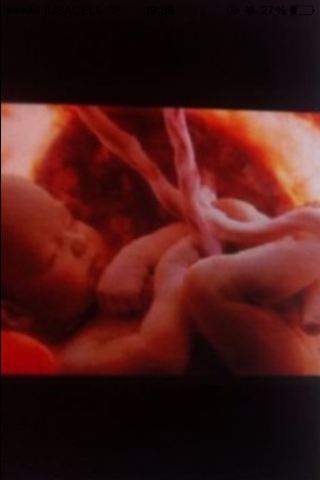

El bebé empezara a buscar la posición para poder nacer

Su peso es de un kilo y medio Links: